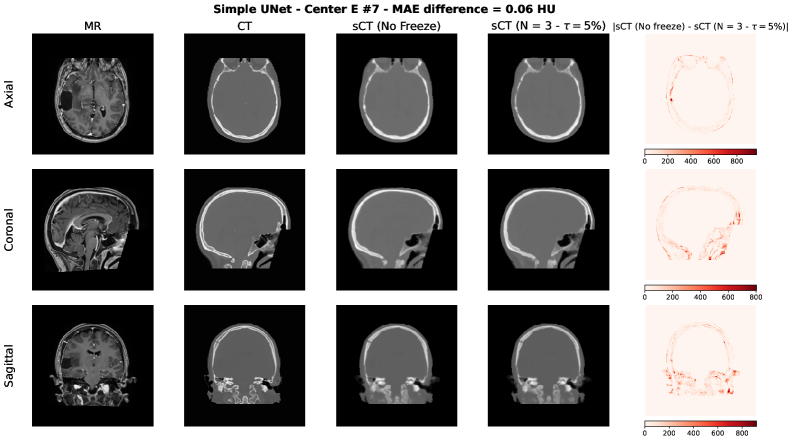

To qualitatively assess the potential impact of the adaptive freezing strategy on the generated synthetic CTs (sCTs), we conducted a visual comparison between the sCTs obtained with and without the proposed methodology. For each model employed in the study, we selected two representative test cases based on the following criteria:

• The case with the minimum difference in terms of MAE, thus the lowest difference between the sCTs MAE generated with and without adaptive freezing.

• The case with the maximum difference in terms of MAE, thus the highest difference between the sCTs MAE generated with and without adaptive freezing.

Each figure presents the following for the axial, coronal and sagittal plane of the central slice:

1. 1.

Input MR image;

2. 2.

Ground-truth CT image;

3. 3.

sCT generated without adaptive freezing;

4. 4.

sCT generated with the proposed adaptive freezing, using 𝒩=3\mathcal{N}=3 and τ=5%\tau=5\%;

5. 5.

Absolute difference map between the two sCTs.

Figure S1: Simple UNet [35] – Minimum MAE difference case.

Refer to caption

Across all models and both selected cases, no relevant and systematic structural differences were observed. The differences highlighted in the absolute difference maps and the variation in MAE are attributable to the stochastic nature of the training process (e.g., batch shuffling and optimization path variability) rather than the direct effect of the adaptive freezing mechanism.

This findings are aligned with the results observed in terms of MAE, PSNR and SSIM presented in this study.